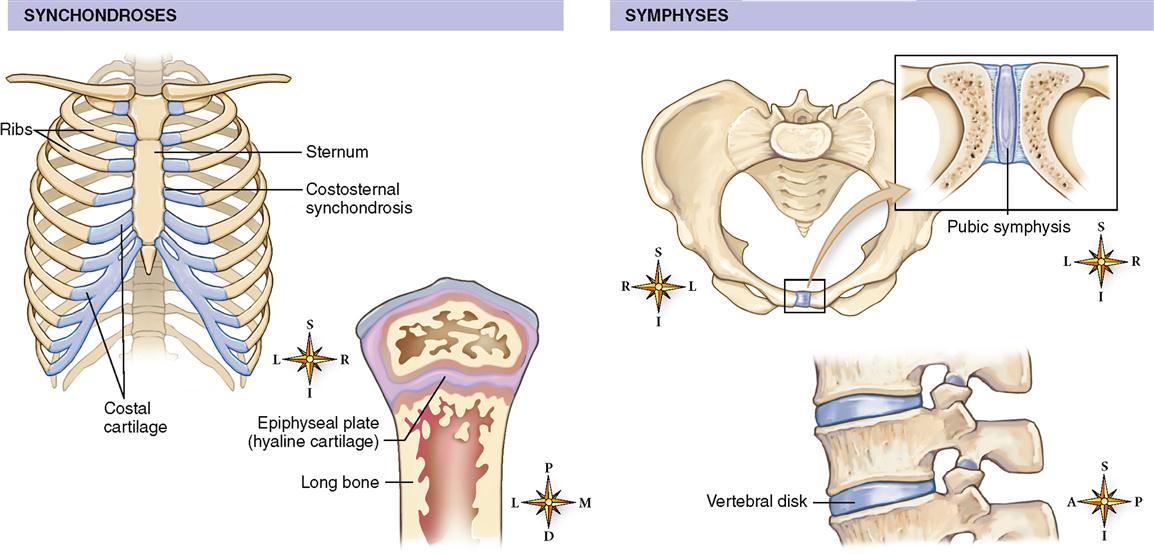

Структура и анатомия синдесмоза: научные иллюстрации